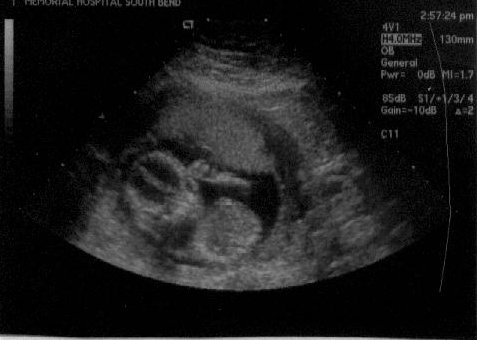

| Finally, ultrasound pictures worth looking at!! On both pictures, the head is the sphere on the left, and the body is the sphere on the right. You can also clearly see the arm and hand above the two spheres in both pictures. In fact, in the right picture, it appears that the baby might even be sucking on its thumb. The tech said everything looked great, and the baby has actually now progressed to measuing a whole week ahead! I am only 15 weeks 3 days today, but the baby is measuring 16 weeks 3 days. Click here to read more about the results of the ultrasound. (June 6, 2002 - 15 weeks, 3 days) |